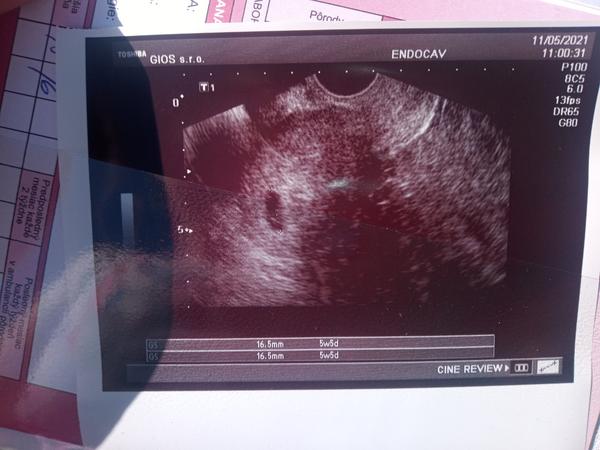

Som tu zase :( posledná ms 24.3 to bola prvá menštruácia po spontánnom potrat cyklus mám 30-35 Ďalšia neprišla 26.4 hcg50 3.5 hcg 1760 dnes sono kde nebolo nič vidieť povedal dr že samu tam niečo zdá ale mám pocit že to preto lebo vie že to ťažko znasam. Zajtra opäť na krv opäť som hotová už nevládzem beriem medrol duphaston picham si clexane veľmi sa bojím 😭😭😭😭😭😭😭